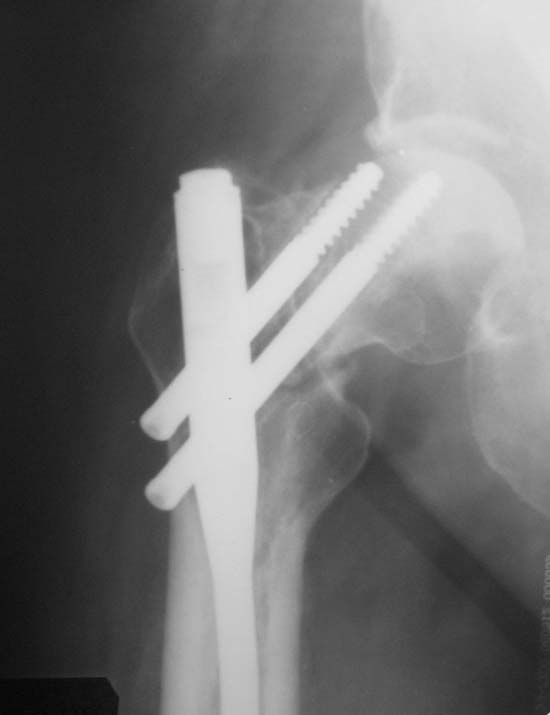

Пациент (мужчина), 34 года. Травма в результате ДТП в апреле 2011 года. Проводилось оперативное лечение – закрытая репозиция, остеосинтез AFN. В октябре 2011 года – декортикация, тунелизация, фиксация отломков верхней трети диафиза бедренной кости проволочным серкляжом, удаление дистального блокирующего винта. На контрольных рентгенограммах определяется миграция шеечных винтов конструкции. Пациент передвигается на костылях с дозированной нагрузкой на ногу (полная нагрузка болезненна в области тазобедренного сустава). Вариант лечения - тотальное эндопротезирование тазобедренного сустава+остеосинтез верхней трети диафиза бедренной кости (ретроградным стержнем ЦИТО, пластиной, АНФ).Жду Ваших комментариев

Вроде признаков асептического некроза головки не видно. Думаю подвертельная остеотомия с устранением варуса с фиксацией 95 гр пластиной + ретроградно стержень с рассверливанием канала.

Добрый день! Думаю, что все предшествующие проблемы из-за некорректной установки данной металлоконструкции. Не надо было добиваться красивой рентгенкартинки используя серкляжи и т.п.. Устранены все виды смещения - этого уже достаточно (один из основных принципов БИОСА сохранение перирефрактурной гематомы, нарушив периоссальную васкуляризацию с интрамедуллярной- получили замедленную консолидацию). К сожалению шеечные винты даже с поправкой на их миграцию тоже утановлены не совсем корректно. Но это по большому счёту бывает у каждого, кто хорошо работает, ошибок нет если ничего не делать. В данной ситуации ставить протез на длинной ножке, убирая из фнкции половину нормальной бедренной кости у молодого 34-х летнего человека считаю абсолютно нецелесообразным. Конечно полной информацией о данном больном не владею, но думаю, что на данном этапе только реостеосинтез, Любой длинный проксимальный вертельный стержень, большего диаметра (Де-пьюшный Афиксус, страйкеровскую Гамму и т.д., принципиального значения не имеет, что возможно в Ваших условиях), с рассверливанием интрамедуллярного канала и корректной установкой шеечных винтов, с выведением нормального шеечно-диафизарного угла и умеренной компрессией на шеечном винте шейки бедренной кости. Установку провести в динамическом варианте и дозированную нагрузку сразу. Думаю проблему с диафизом Вы решите, что касается шейки-решать по мере поступления, если встанет вопрос через некоторое время об энопротезировании, то это будет классический тотальник, без удлинённых ножек, с типичной техникой операции эндопротезирования, что думаю важно для 34-х лет.

Головка вроде еще живая, думаю стоит побороться за сустав. Подвертельная корригирующая остеотомия короткой гаммой или отмоделировать LCP с 2 винтами в шейку. На диафиз LCP MIPO или ретроградный штифт с блокированием.